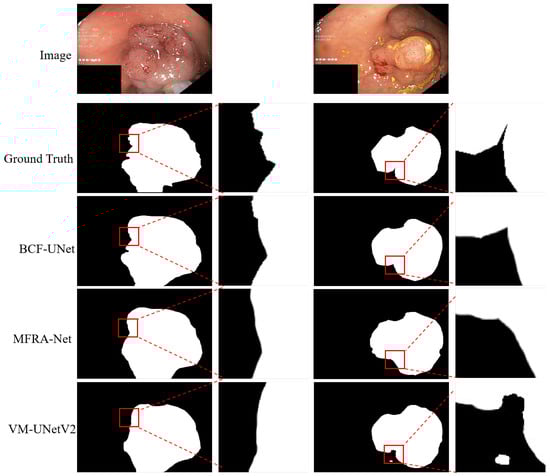

4.5. Qualitative Analysis